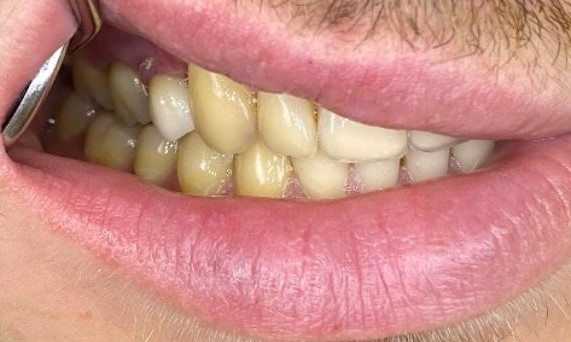

Exzellente Ästhetik

Langfristiger marginaler Knochenerhalt für eine exzellente Ästhetik über Jahre hinweg. Sie wissen, dass Sie gewonnen haben, wenn Ihr anspruchsvollster Patient dauerhaft zufrieden ist.